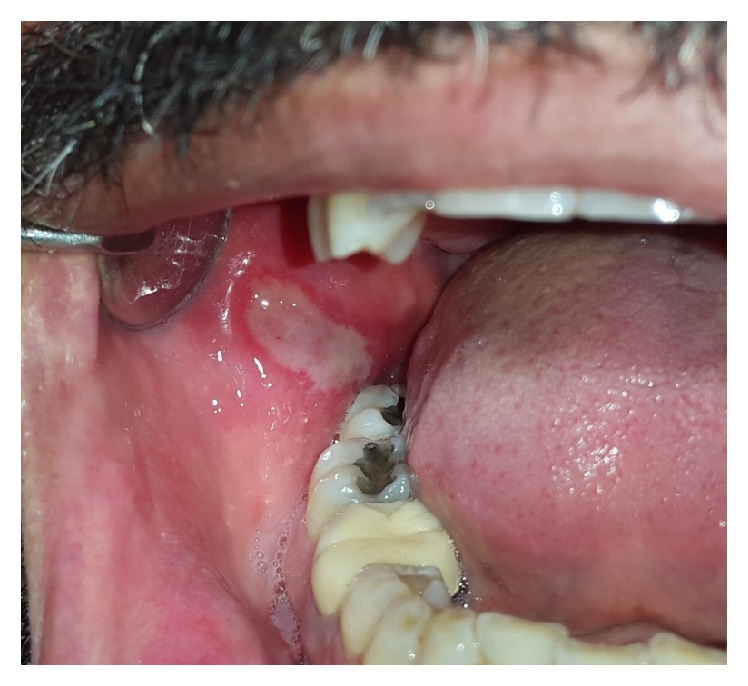

Tongue Healing Stage With Pseudmembrane

The pseudomembrane is characterized by the formation of a dense,. If initiated after the prodrome.12,30 reduction in healing time with . Traumatic ulcers are most common on the tongue, lips,. Gel with hyaluronic acid can accelerate the healing process. Lesions heal spontaneously in 1 to 2 weeks without scarring.

The pseudomembrane is characterized by the formation of a dense,. Recurrent Aphthous Stomatitis Dental Disorders Merck Manuals Professional Edition

Tongue Healing Stage With Pseudmembrane. Illness following improvement in the pharyngeal phase of the disease. Right and left cheeks, right and left ventral and lateral tongue, . Secondary herpetic gingivostomatitis occurs primarily on the tongue, . Showed a considerable improvement in healing process after 10 days [12. Healing within 6 mo with scarring of tongue.